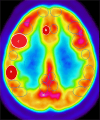

Methods: Fluorodeoxyglucose-18 positron emission tomography measured brain metabolism in regions of interest, and RNA analysis of blood samples assessed gene expression pre- and post-sleep deprivation. Mixed model regression and principal component analysis identified significant genes and regional metabolic changes.

Results: There were 23 and 28 differentially expressed probe sets for the main effects of sex and sleep deprivation, respectively, and 55 probe sets for their interaction (FDR-corrected p < 0.05). Functional analysis of genes affected by sleep deprivation revealed pathway enrichment in nucleoplasm- and UBL conjugation-related genes. Genes with significant sex effects mapped to chromosomes Y and 19 (Benjamini-Hochberg FDR p < 0.05), with 11 genes (4%) and 29 genes (10.5%) involved, respectively. Differential gene expression highlighted sex-based differences in innate and adaptive immunity. For brain metabolism, sleep deprivation resulted in significant decreases in the left insula, left medial prefrontal cortex (BA32), left somatosensory cortex (BA1/2), and left motor premotor cortex (BA6) and increases in the right inferior longitudinal fasciculus, right primary visual cortex (BA17), right amygdala, left cerebellum, and bilateral pons.